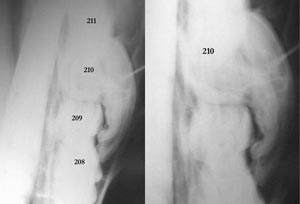

A common site for congenital anomalies of the digestive system is dentition. Many of these defects are present but not observable at birth so they are atypical congenital defects that don’t appear for months or several years after birth when various teeth erupt (or don’t erupt!). For this reason, the Kentucky study of congenital defects in foals does not list dental defects (AJVR 46: 353-358, 1985). Most equine veterinarians agree that dental defects are more common in smaller horses, especially miniature horses. Apparently, selection for small size resulted in a head too small for the teeth therein. In other words, it is easier to select for small bones than for small teeth. As a result, malocclusions can occur as some cheek teeth erupt and don’t have enough space to erupt into. Other common defects are polydontia (extra teeth) and oligodontia (missing teeth).